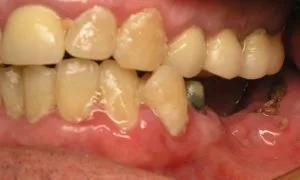

Periodontal Disease – Infected Gums – Gum Abscess

Periodontal disease results from untreated gingivitis. And what separates the two is the damage to the foundation of the tooth. With gingivitis, the damage is only to the gum tissue around the tooth. With periodontitis, the damage extends further into the bone and down to the connective tissue. Teeth look longer as the gums pull away. Gums bleed and are generally tender. Some teeth will become noticeably looser. And there will come a time when the teeth are so wiggly that nothing can save them.

Gum abscess can occur during periodontitis. What happens is that the infection and pus keep building up underneath the gums. Since the pus is growing in a closed space and can’t drain away, the pus volume keeps increasing. The buildup of this infection causes the gums to bulge out as a result of the pressure.

Gum disease leads to tooth loss. The disease is also tied to other systemic ailments like heart disease, diabetes, and pregnancy complications. Gums disease starts with the formation of plaque on the teeth. When the patient doesn’t remove the plaque, the gums start getting out of control.